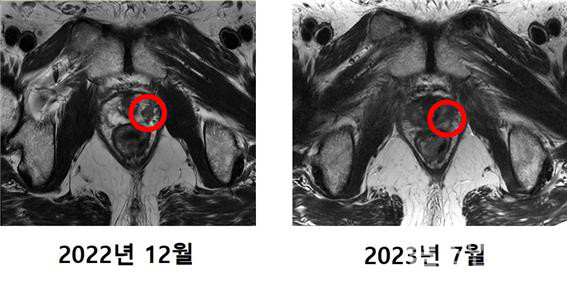

4월 말 치료를 시작한 최씨는 한 주에 3~4회씩 총 12번의 치료를 거쳐 5월 중순 모든 치료를 마쳤다. 치료 후 최씨의 PSA 수치는 0.01ng/mL 미만으로 떨어졌고, MRI 촬영 결과 암 조직은 발견되지 않았다.